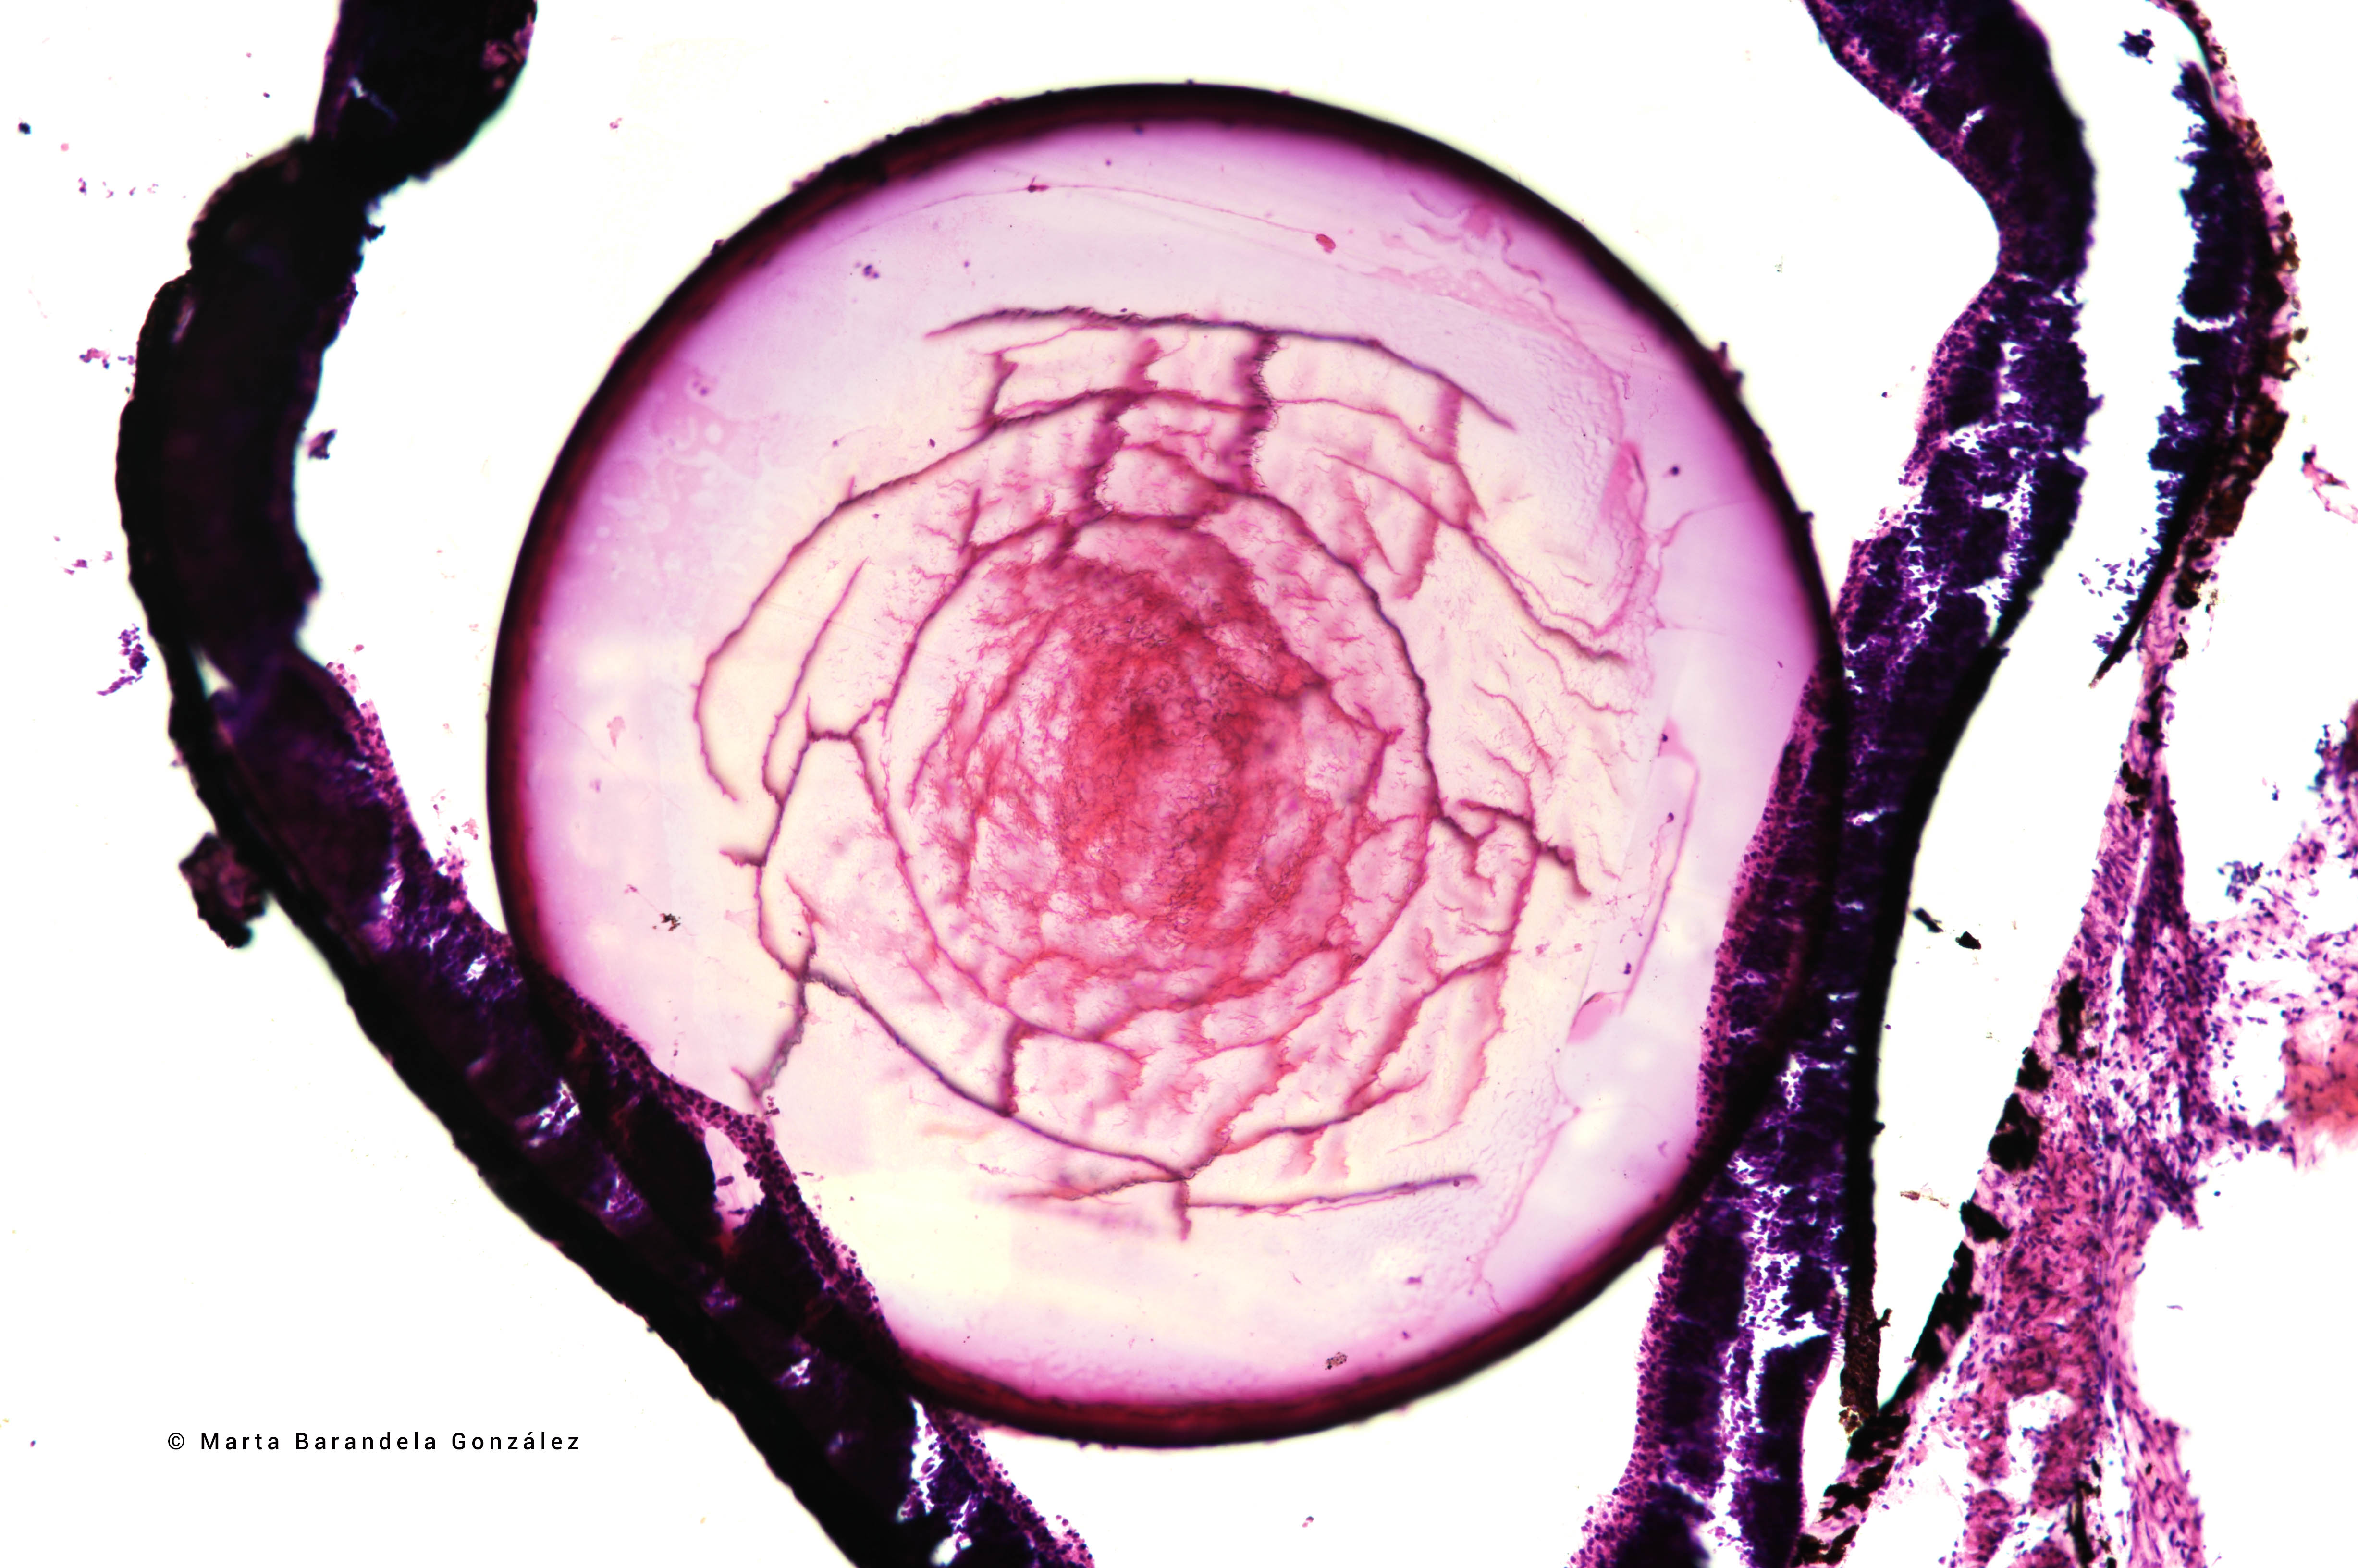

A investigadora Marta Barandela, primeiro premio no concurso de fotografía do CINBIO 2023

19 decembro 2023